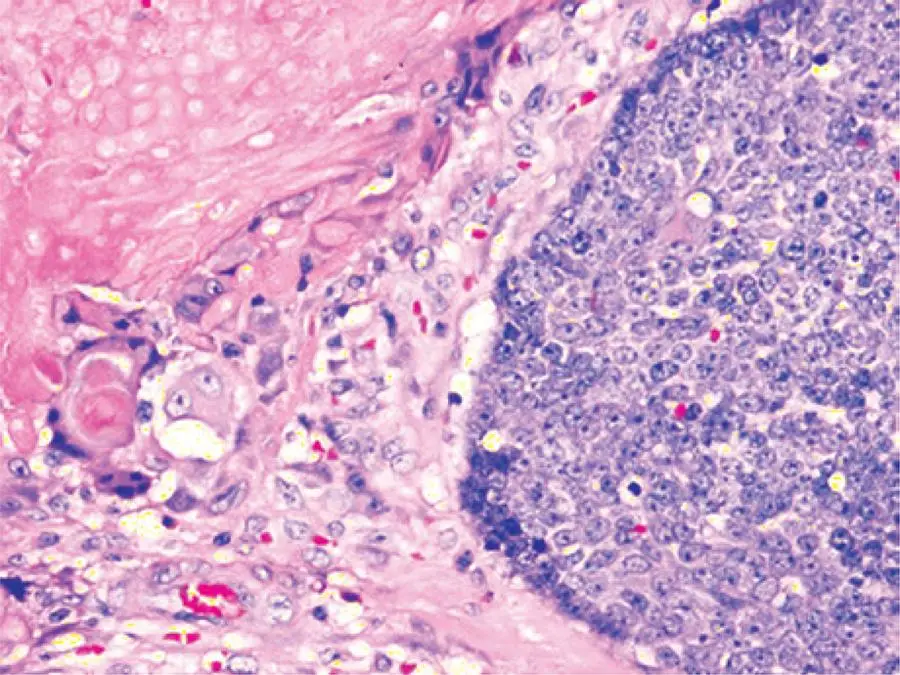

A 10-year-old girl presented with a painless, slow-growing swelling on left pre-auricular region that was noticed for 2 years (). The swelling was bosselated, non-tender, firm-to-hard on palpation, had poorly-defined margin, and measured approximately 3.5cm x 3.0cm. In addition, it had restricted mobility, and seemed to be of parotid origin, with overlying skin apparently stretched and fixed. The ultrasonography was unable to delineate the depth and confirm the involvement of the parotid, although fine needle aspiration cytology (FNAC) suggested pleomorphic adenoma. For this reason, we decided to perform superficial parotidectomy. The histopathology of the lesion diagnosed pilomatricoma, which is an uncommon, benign ectodermal tumor of dermis/subdermis. Pilomatricoma constitutes a pluripotent cell expression in the germinal matrix center of hair follicles with differentiation into cortical cells, and the main relevance of its clinical presence is its potential to be misinterpreted, resulting in unnecessary aggressive interventions. It is often a diagnosis of retrospection. Some large series reported correct pre-operative diagnosis at 1.1 to 29%.(,) A careful re-examination of pre-operative image revealed a subtle bluish tinge, which was not observed presumably because of the dark-skinned complexion, and the characteristic “tent sign”() perceptible through the already-stretched and bosselated skin surface (). Fine needle aspiration cytology is imperative for the assessment but is often erroneous() due to inadequate, non-representative sampling from a lesion with complex cell contents. In a typical example, the basophilic basaloid cells with scanty cytoplasm and indistinct borders encase the anucleated cytoplasm-rich eosinophilic “ghost/shadow cells” () with areas of keratinization, giant-cells and dystrophic calcification in the matrix. As the tumor gets older, the central “ghost cells” increase at the expense of the peripheral basophilic cells. Thus, FNAC might have more basophilic cells in the lesion in early stages while keratinocytes might predominate in later stages, so that the lesion can be misrepresented as malignant in both stages.() The problem is complicated by the fact that the parotid region is one of the most common topographic areas with involvement of head and neck pilomatricomas,(,-)which also increase the dilemma of clinicians and pathologists because pilomatricoma is seldom considered as a differential diagnosis for a mass lesion involving this region. In fact, some reports on FNAC from such lesions had suggested parotid neoplasm,() or even metastatic malignant deposits.() Because surgeons relying greatly on cytology in clinically suspected parotid tumors, such approach have resulted in more aggressive surgical treatment.(,,)